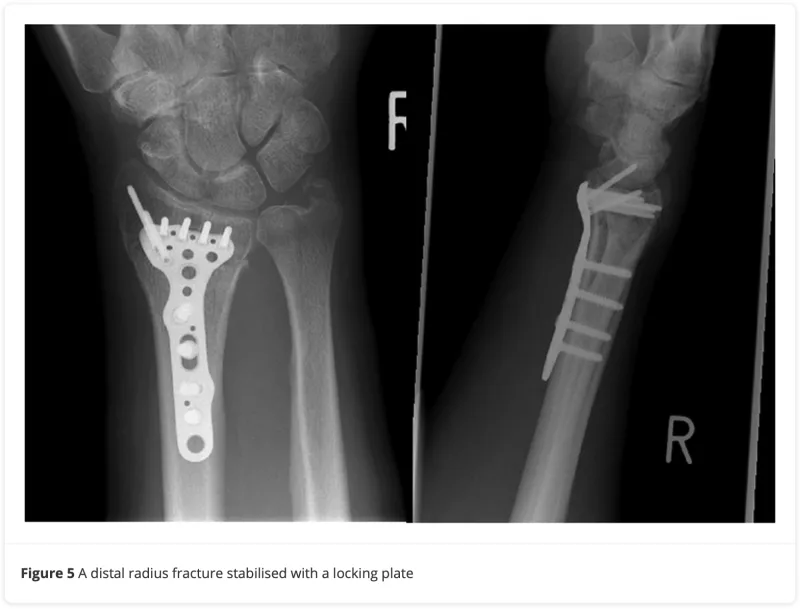

本日の手術は掌側Barton骨折。

引用元:Lim JA. Perioperative management of distal radius fractures. J Perioper Pract. 2020. 31.

橈骨遠位端に解剖学的形状の金属製の板(掌側ロッキングプレート)をあてて, スクリューで固定する方法です.